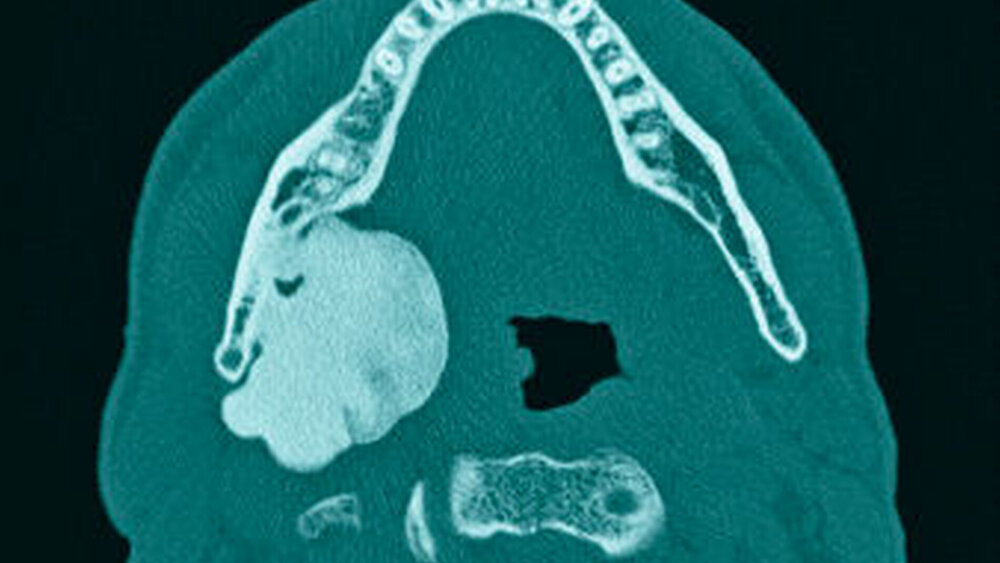

Im mitgebrachten alio loco erstellten Orthopantomogramm war eine gut abgrenzbare, ovale, homogene Verschattung zu sehen, welche sich im Bereich des rechten Kieferwinkels, in dorsaler und kranialer Richtung über diesen hinaus sowie im Bereich des aufsteigenden Unterkieferastes bis kaudal unter die Incisura semilunaris erstreckte (Abbildung 1). Computertomografisch war ausgehend von der medialseitigen Corticalis des Angulus mandibulae rechts eine irregulär, angedeutet rundlich konfigurierte, glatt begrenzte knöcherne Raumforderung von circa 4,4 x 3,3 x 4,7 cm Größe zu sehen (Abbildungen 2 und 3). Diese führte zu einer Verlagerung der Anatomie, insbesondere zu einer Vorwölbung der rechtsseitigen Oropharynxseitenwand (Abbildung 4). Es bestanden keine Hinweise auf eine knöcherne Destruktion oder auf eine Lagebeziehung zu einem Zahn.